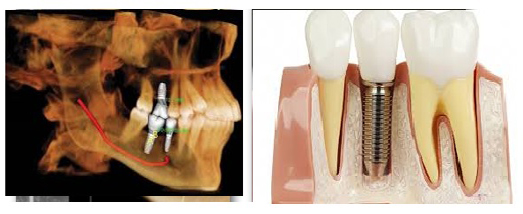

Implants

• Accurately determine bone height and width

• Determine bone quality (HU statistics)

• Accurately determine long axis of alveolar bone

• Identify and localize internal anatomy – inferior alveolar canal, maxillary sinus floor, mental foramen, incisive canal, etc

• Precisely determine jaw boundaries

• Pathology detection